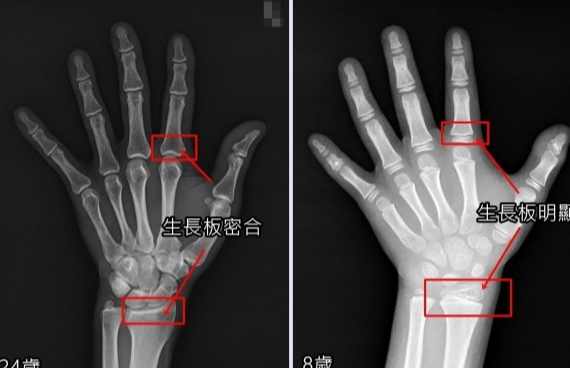

先來點基礎知識。生長板(Growth Plate)其實是長骨兩端的軟骨組織,它是我們身高增長的核心引擎。這東西就像個神奇的工廠,不斷生產新的骨細胞,讓我們從小豆丁慢慢抽高。

但問題是,這個工廠有營業時間限制。一般來說,女生在14-16歲、男生在16-18歲左右,生長板就會開始閉合。閉合後,骨頭就停止縱向生長,這也是為什麼很多人覺得青春期後就不可能再長高。

不過這裡有個常見誤區:生長板閉合不是瞬間完成的,而是個漸進過程。這就給了我們一些操作空間,關鍵是要抓住閉合前的最後機會,或者利用其他方式刺激殘餘的生長潛力。